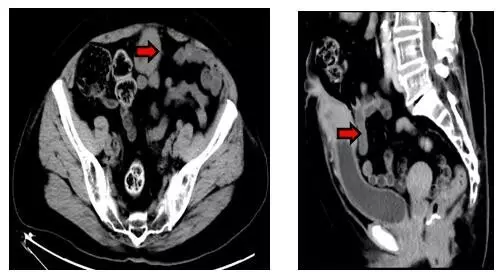

疾病早期未重视,寻医三院病症除

本例患者不是男性而是71岁女性,因“脐部溢液并下腹部红肿硬块”前来就诊,之前也曾到过医院但并未引起足够的重视。家属找到杨伟忠主任医师后,经仔细询问病史并检查病人,杨主任马上诊断是脐尿管的慢性病变,并且高度怀疑肿瘤的可能性。立即给予下腹CT检查报告为:“下腹部正中线区域脐-膀胱顶部之间软组织肿块影,性质待定:脐尿管肿瘤?炎症性病变?(见下图)”。

入院后我们对患者进行全面的身体状况评估、认真研究影像学资料确定病灶的范围以及与邻近脏器的关系、排查膀胱内病变后,顺利施行了标准的根治性切除手术。